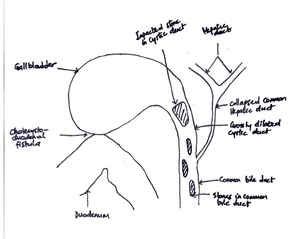

On examination, she was in fair general condition, afebrile and not icteric. The abdominal exam was normal. All relevant laboratory investigations were within normal ranges, and we proceeded with laparoscopic cholecystectomy. Intraoperatively, we noted extensive adhesions involving the gallbladder, omentum, and bowel. The gallbladder was firmly adherent to the cystic plate, rendering the surgery difficult. This prompted the team to opt for a bailout subtotal cholecystectomy. After dividing the gall bladder at the neck, a cholecystoduodenal fistula (Figure 3) less than 5mm was noted along with some bile leaks in the surgical field, reducing visibility. This led to the conversion to an open procedure through a midline incision. The duodenum was primarily repaired and secured with a pedicled omental flap. In an attempt to clearly define the biliary tree anatomy, we decided to explore the CBD. We made a 2cm incision on the anterior aspect of the CBD, which revealed a patent plastic stent in situ and multiple stones. The cystic duct was grossly dilated and found to be in continuity with the CBD. It contained multiple impacted stones, the largest measuring approximately 3cm. All stones were successfully extracted. A bile leak was noted at the cystic stump and was repaired primarily. The CHD was almost collapsed. The presence of a cholecystoenteric (cholecystoduodenal) fistula in a context of MS without gallstone ileus made us classify this as a Type 5A according to Csendes classification (Figure 4). The CBD was then repaired primarily. Abdominal irrigation was done, and a drain was left in situ. Postoperative monitoring was negative for bile leaks. The patient improved clinically, with liver function test normalising and was discharged after 10 days. Clinic follow-ups were scheduled every 3 months. The patient remained asymptomatic and is currently doing well and improving.